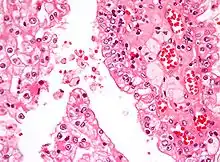

![]() Micrografía que muestra el tipo más común de cáncer de riñón (carcinoma de células renales de células claras). Tinción H&E. | ||

El tipo más común de malignidad renal es el carcinoma de células renales,[33] que se cree que se origina en las células del túbulo contorneado proximal de la nefrona.[15][34] Otro tipo de cáncer de riñón aunque menos común, es el cáncer de células de transición (CCT) o carcinoma urotelial de la pelvis renal.[35] La pelvis renal es la parte del riñón que recoge la orina y la drena en un tubo llamado uréter.[35] Las células que recubren la pelvis renal se denominan células de transición y, a veces, también se denominan células uroteliales. Las células de transición/uroteliales en la pelvis renal son el mismo tipo de células que recubren el uréter y la vejiga. Por esta razón, el CCT de la pelvis renal es distinto del CCR y se cree que se comporta más como el cáncer de vejiga.[35] Otros tipos raros de cáncer de riñón que pueden surgir de las células uroteliales de la pelvis renal son el carcinoma de células escamosas y el adenocarcinoma.[15]